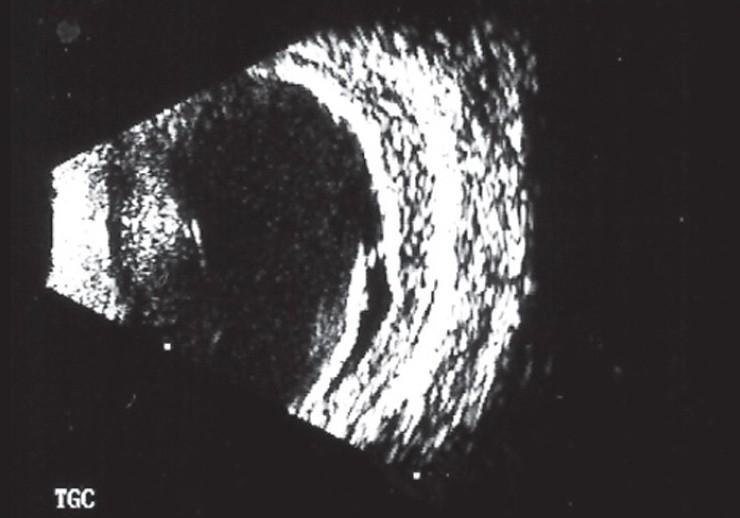

Anterior segment infiltration in acute myeloid leukemia (AML) presenting as hypopyon uveitis is very rare. We report this case as an uncommon presentation in a patient on remission after bone marrow transplant for AML. In addition to the hypopyon, the patient presented with "red eye" caused by ocular surface disease due to concurrent graft-versus-host disease and glaucoma. The classical manifestations of masquerade syndrome due to AML were altered by concurrent pathologies. Media opacities further confounded the differential diagnosis. We highlight the investigations used to arrive at a definitive diagnosis. In uveitis, there is a need to maintain a high index of clinical suspicion, as early diagnosis in ocular malignancy can save sight and life.